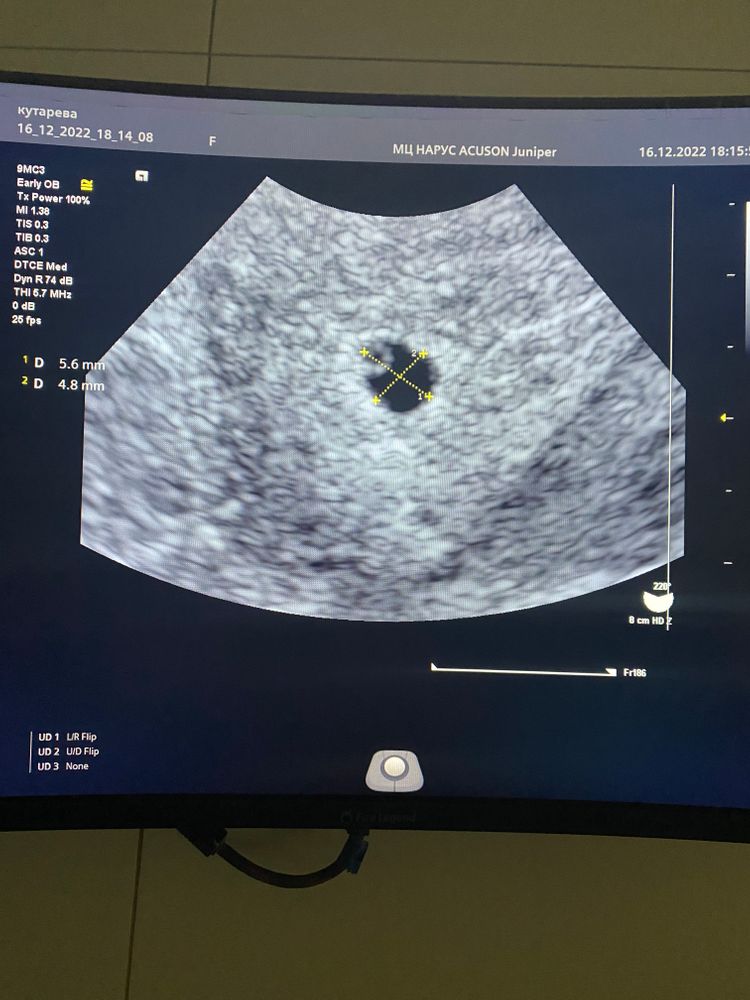

Пошли с мужем на узи:

Мешочек есть, эмбрион малюсенькая белая точка, еле заметная ). Срок Б по М - 5,2 недели.

26.12 пойду на очередное узи для контроля сердцебиения. После праздников встану на учёт)